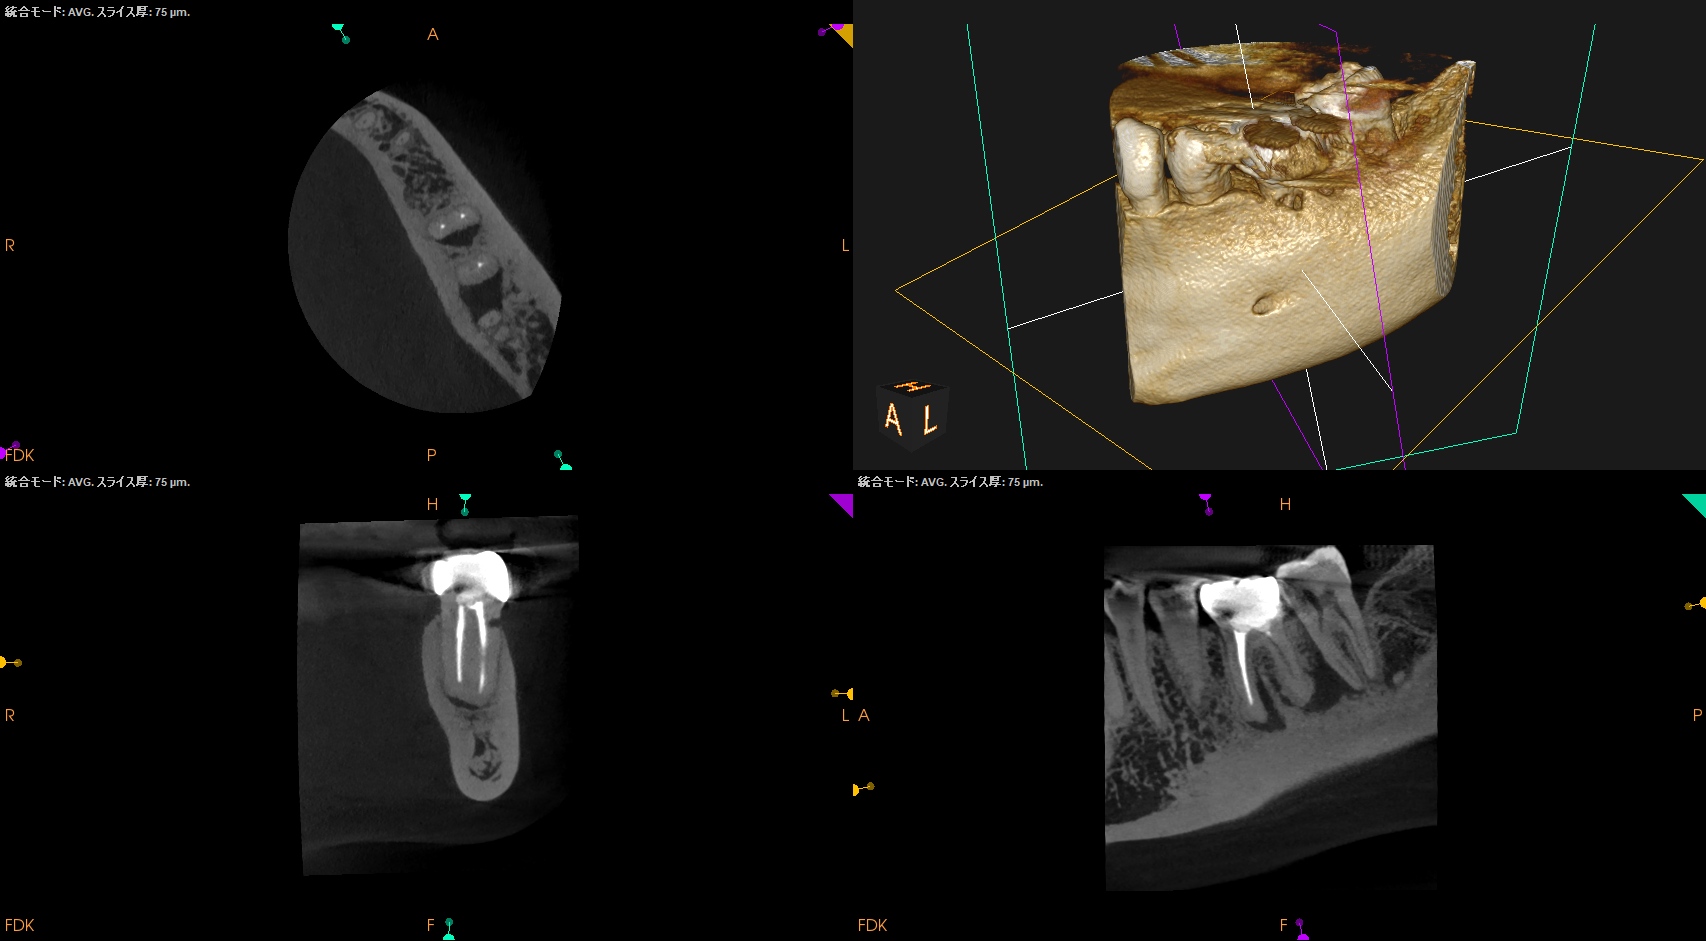

穿孔しているのだろうか?とまず思ったが、CBCTをみてそれは穿孔でなく外部吸収の可能性が高いと判断できた。

もはや全ての歯内療法の処置前には必ずCBCTが必要

という法則が成り立つ。

MBは外部吸収を封鎖する前に根管治療するとヒポクロが漏れて苦いと言われるだろう。

DBはそれはないだろう。

これらの画像的事実と臨床検査から

1. まず外部吸収を封鎖する

2. その後(その日に)、再根管治療を行う

という治療計画を提示し、患者さんが同意していただいたのでまずは外科だ。